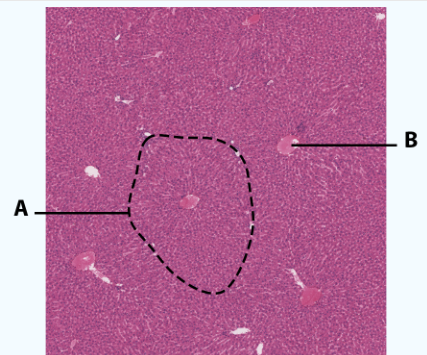

A

Lobule

B

Central Canal

Area

Liver